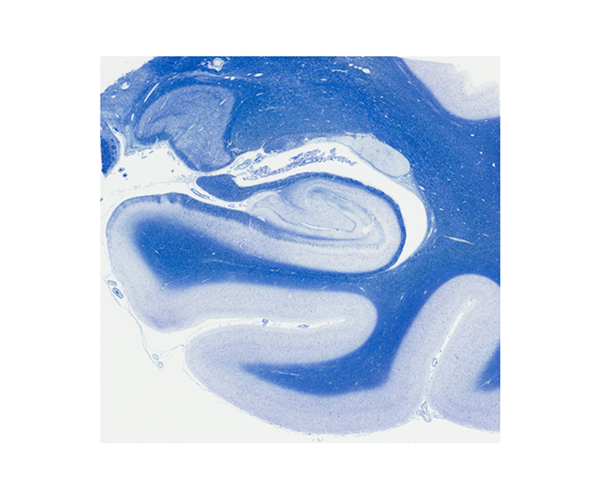

海馬(詳細)

海馬から海馬傍回にかけての領域のおおよそを確認することができる。